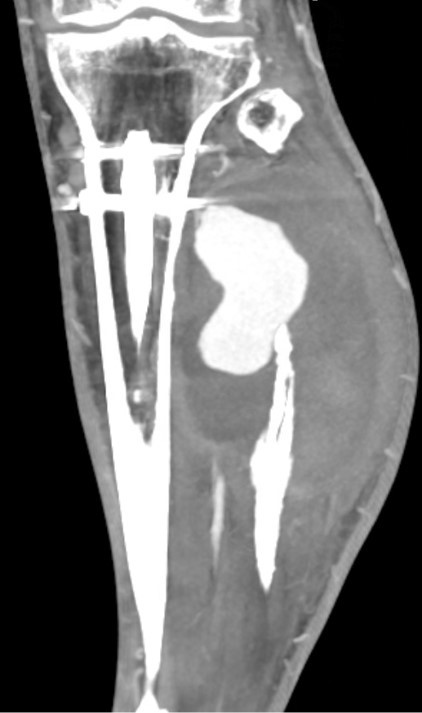

Figure 1: (a) Pre-operative radiograph reveals acute, mildly comminuted fractures of the mid/distal tibia and proximal fibular shaft. (b) Post-operative radiograph reveals intramedullary nailing of tibial shaft fracture in improved alignment and proximal fibular shaft fracture with increased displacement and apex posterior angulation. Upon the present presentation with the increased lateral calf pain and swelling, Doppler ultrasound revealed a large pseudoaneurysm of the ATA with the characteristic yin-yang sign (Fig. 2). CTA confirmed a pseudoaneurysm arising from the proximal ATA, surrounded by a large hematoma in the leg (Fig. 3). The largest aneurysmal sac measured approximately 8.7 × 10.4 × 16.1 cm, with an actively filling, non-thrombosed component measuring about 3.4 × 3.8 × 6.5 cm. Given the significant compressive symptoms caused by the hematoma, coil embolization of the ATA was performed to exclude blood flow into the pseudoaneurysm cavity. Selective catheterization of the left ATA was achieved through ultrasound-guided puncture of the right common femoral artery. Multiple Penumbra Ruby coils were deployed into the proximal and distal segments of the ATA, effectively sealing the pseudoaneurysm defect. A pre- and post-procedural angiogram demonstrated successful cessation of blood flow into the pseudoaneurysm cavity (Fig. 4a and b).

Figure 3: Computed tomography angiography confirms the large pseudoaneurysm arising from the proximal anterior tibial artery, with a surrounding hematoma.